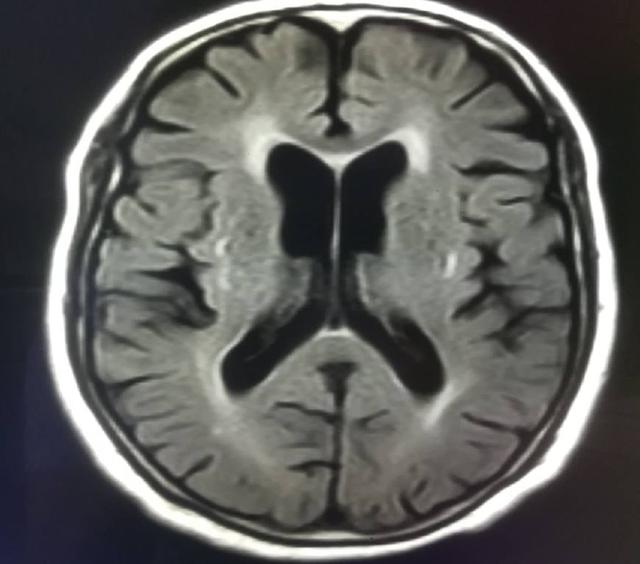

提到大腦萎縮,人們通常都會(huì)想到老年人,的確相比年輕人而言,老年人的大腦萎縮幾率會(huì)增加很多,由于年紀(jì)的增長(zhǎng),人的腦細(xì)胞已經(jīng)逐漸發(fā)育緩慢,萎縮的癥狀會(huì)開始明顯增加,那么老年人腦萎縮能治好嗎?

老年人腦萎縮,可以認(rèn)為是老年人正常生理發(fā)育過程中的一個(gè)階段,如果患者年齡在70周歲以上,出現(xiàn)腦萎縮可以理解為正常的表現(xiàn)。腦萎縮一般來說是不可以逆轉(zhuǎn)的,如果患者出現(xiàn)明顯的記憶力下降、反應(yīng)遲鈍等癥狀,就需要立即展開相關(guān)治療了。